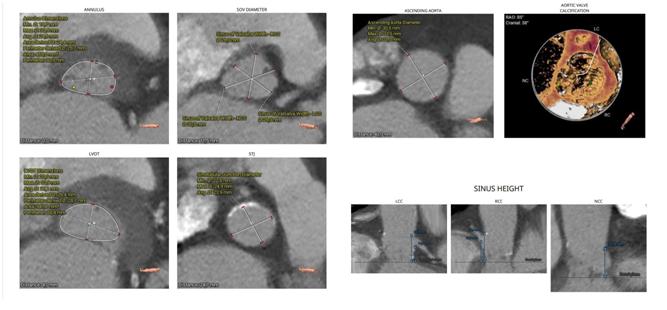

Ciddi aortal çatışmazlıqla bağlı kardiogen şok xəstədə TAVI